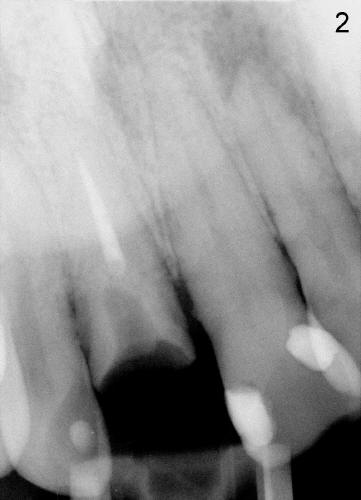

Salvageable or not (2)?

A 37-year-old otherwise healthy gentleman presented to clinic for extraction due to multiple times of crown failure (Fig.1,2). It appears that crown margin is ~2 mm supragingival. After RCT retreatment and fabrication of cast post & core, the tooth seems to be salvageable. But the patient was adamant in extraction and implant restoration.

Finally the tooth was extracted. In fact, it is indeed nonsalvageable. Can you guess what is the main reason for non-salvageability?